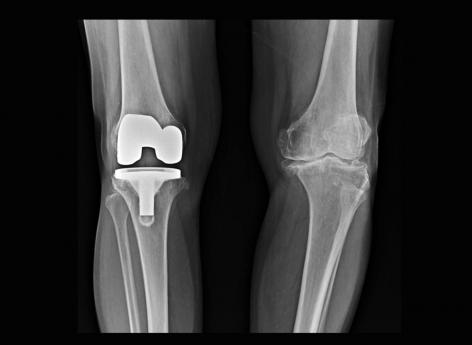

Une opération chirurgicale pour mettre une prothèse du genou peut être proposée aux personnes souffrant d’arthrose mais uniquement si les autres traitements médicamenteux ne fonctionnent pas. Dès lors que la décision est prise, il existe différents types de prothèses, dont celles totales ou unicompartimentales - quand un seul compartiment du genou est touché par l’arthrose-, par exemple. La mise en place de ce type de dispositifs médicaux permet aux patients de retrouver une mobilité de flexion presque complète et une vie quotidienne normale incluant, s’ils le souhaitent, la pratique d’une activité physique. Néanmoins, la reprise sportive doit être progressive en post-opératoire et suivie par un professionnel de santé comme un kinésithérapeute.